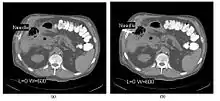

CT Fluoroscopy

- CT Fluoroscopy (CTF) has also been referred to as Continuous CT or Real-Time CT since it involves generating tomographic images at sufficiently high frame rates to allow guidance of needle placement in small or deep-seated lesions. Applications can include biopsy of thoracic lesions, biopsy/drainage of pelvic lesions, vertebroplasty and drainage/aspiration of intracranial haematomas. The advantages of CTF include increased target accuracy and reduced procedure times[45].

- The value of N is typically 30o, 45o or 60o, with frame rates of 12, 8 and 6 frames per second, respectively. In the case of 60o updates and 6 frames per second, the delay between each image is 0.17 seconds. A Last-Image-Hold (LIH) technique can be used while the image is being updated with the resulting time lag being considered by the interventionist in terms of biopsy technique. Example images are shown in Figure 7.15.11. The display of three adjacent slices of thickness 5 mm with MDCT scanning can be used to improve visual feedback to the interventionist as the needle progresses. In addition, multi-planar reconstructions (MPR) and volume rendered 3D images can be used to enhance fine control.